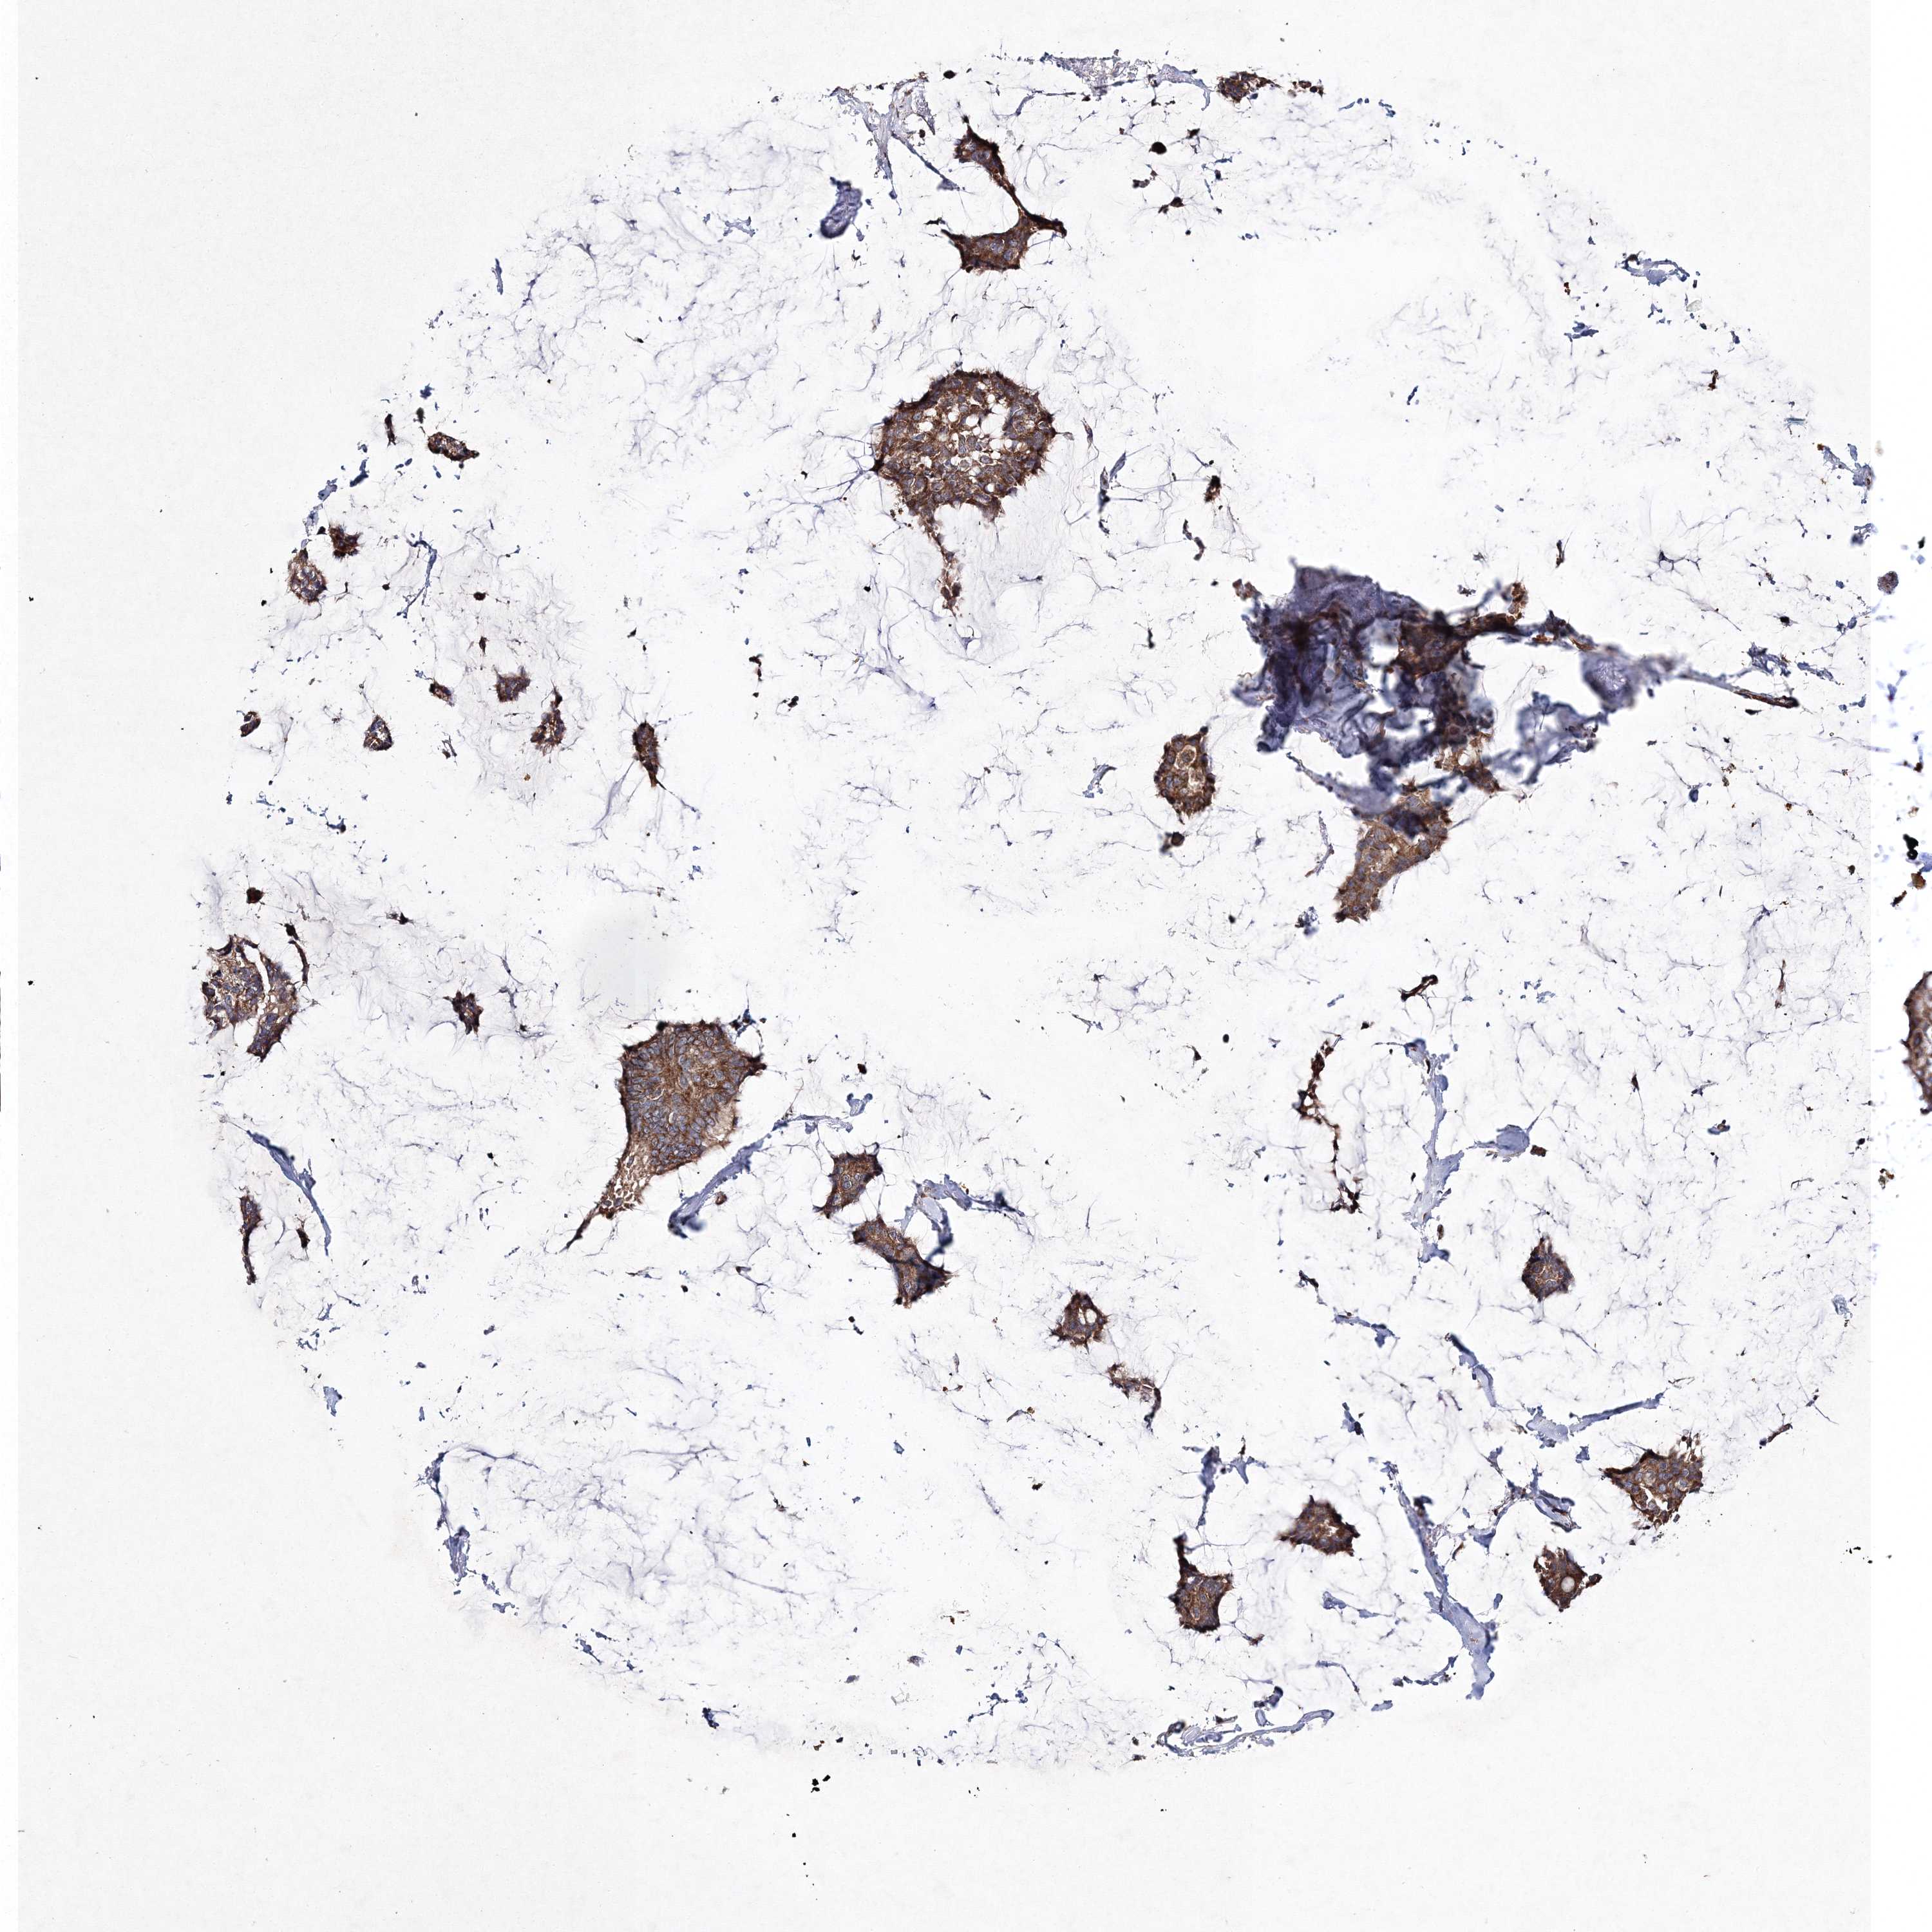

CANCER BREAST CANCER Show tissue menu

BRCA TCGA BRCA VALIDATION PROTEIN EXPRESSION